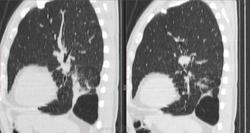

КТ:

Добавила КТ в начале случая. Контрастирования не было, не будет. Дайком тут: http://files.mail.ru/0KS7TD   22,3 МБ объём

Выставила интралобарную секвестрацию. Пациент консультирован в областном центре, дополнительных методов обследований там не выполнялось, посмотрели дайком нативной КТ ОГК и согласились.

При просмотре ФЛГ видела кисты/буллы и ненормальный левый корень. Полосу за тенью сердца приняла за шварту. Взяла на КТ, чтоб разобраться, связан ли куцый корень и кисты. Секвестрация оказалась сюрпризом. Решила, что всё-таки аномалия со своей плеврой. Насколько смогла разобраться на нативном исследовании, все бронхи на месте, а дополнительное образование с кистами и каким-то зачатком бронхиальной системы - ниже S6 и медиальнее S10. С темой секвестрации знакома по детским случаям коллег.

Уважаемые коллеги, внимательно ознакомился со ссылками. Вот что понял (возможно, понял неправильно): секвестрация - скорее плотность, чем полость, в данном случае - скоре полости, чем плотности. И второе: бывают ли секвестрации множественными? В данном случае,  патологические плотности в разных отделах левого легкого.

Секвестрация - мини-лёгкое в лёгком, с кистами, участками консолидации и в различной степени пневматизированное образование.

Второе - кишка.